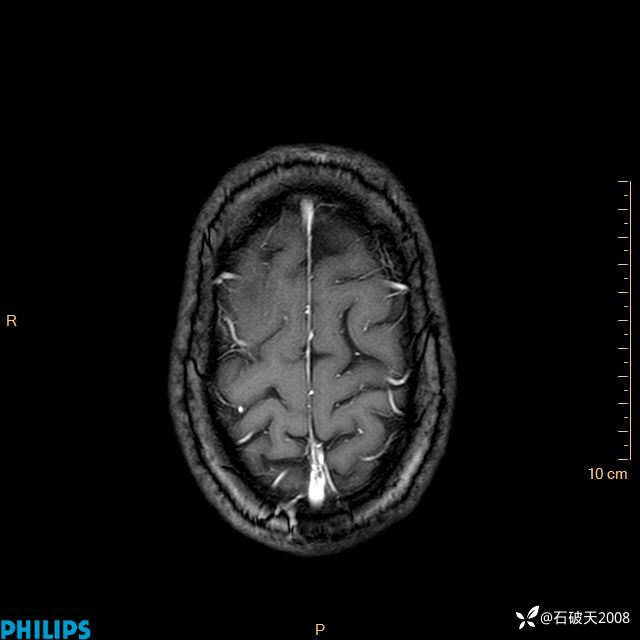

2024.2.21MR

增强轴位

增强冠状位

增强矢状位